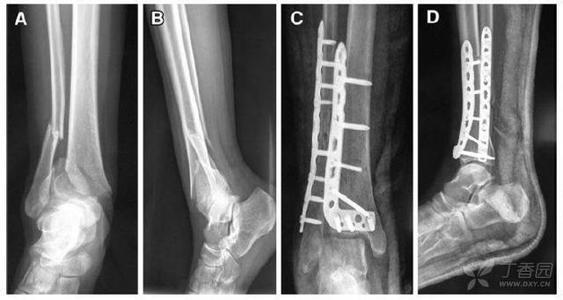

刚刚得到消息说,博古特经过 X 光检查,确定博古特的伤势是左腿胫骨骨折,但是骑士还没公布他的休战时间有多长。

胫骨是小腿上那根粗的骨头,是支持小题的主要骨头,也是连接大腿的骨头,这根骨头骨折少说要一、二个月的治疗,看样子博古特赛季是要报销了。